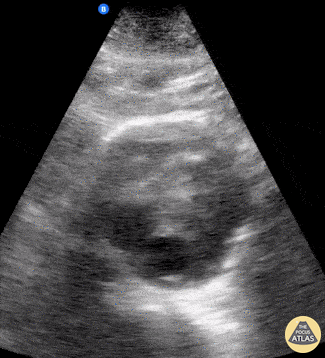

Aorta - AAA

Emergency response was called for an 88-year-old who experienced sudden onset thoracic and back pain. PMH significant for AAA (previously measuring 5.8 cm diameter on surveillance imaging 1 year ago). Mid-abdominal US view was obtained (shown here) and revealed AAA now measuring 7.2 cm diameter. Wolfgang Geisser @fentanyl05